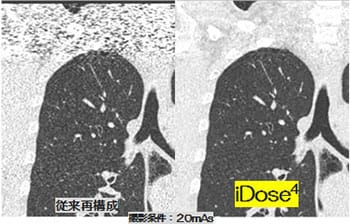

フィリップス独自の逐次近似応用再構成技術iDose4により、検査の目的・部位・撮影条件など必要に応じてノイズ低減ができ、さまざまな臨床応用を可能とします。医療被ばく低減施設として、高画質な画像をより低い被ばく線量で撮影することができます。